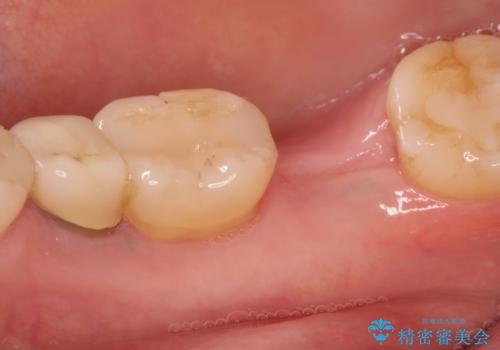

- 右下の奥歯をかぶせ物がとれたまま放置しているところに歯を入れたいとのことで来院されました。

精査すると保存が難しいため抜歯をして、インプラントを埋入、かぶせ物を装着する計画としました。

インプラント治療により、周りの歯を削ることなく咬合を回復することができました。